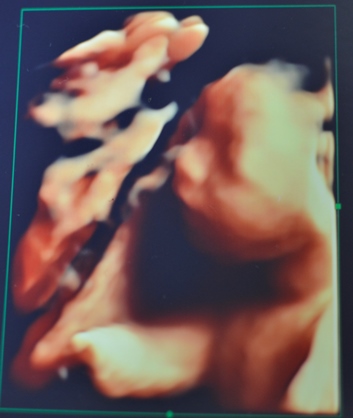

さて、話を戻して今日のエコー写真です。

だいぶ人間の顔してきましたねー。

性別ですが…前回は女の子70%と言われましたが、

本日担当した先生は

「んー男の子かなぁ?微妙ですねー、また今度ね」

と言われ、

すっかり女の子気分だったんですが、

男の子説が再浮上してきました(^_^)

まぁ元気な子であればどちらでもいいのですが、

まだお楽しみは先に取っておく必要があるようです…。